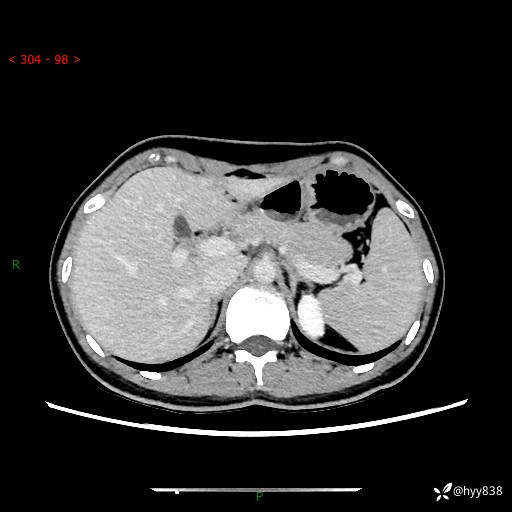

性别:女

年龄:23岁

简要病史:外院发现肝结节,来我院进一步增强确诊

上腹部CT平扫+增强

肝囊肿 (68)